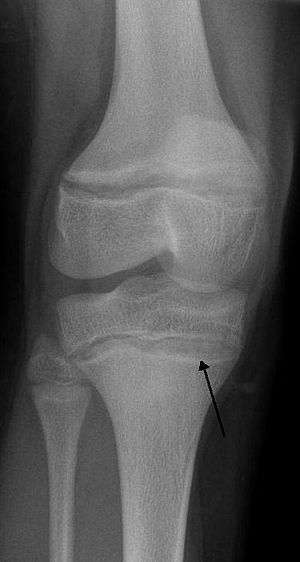

An X ray demonstrating the characteristic finding of lead poisoning in humans—dense metaphyseal lines.

Exposure to lead can occur by contaminated air, water, dust, food, or consumer products. Children are at greater risk as they are more likely to put objects in their mouth such as those that contain lead paint and absorb a greater proportion of the lead that they eat.[1] Exposure at work is a common cause of lead poisoning in adults with certain occupations at particular risk.[3] Diagnosis is typically by measurement of the blood lead level.[1] The Centers for Disease Control (US) has set the upper limit for blood lead for adults at 10 µg/dl (10 µg/100 g) and for children at 5 µg/dl.[4][5] Elevated lead may also be detected by changes in red blood cells or dense lines in the bones of children as seen on X-ray.[6]

Blood lead levels are an indicator mainly of recent or current lead exposure, not of total body burden.[147] Lead in bones can be measured noninvasively by X-ray fluorescence; this may be the best measure of cumulative exposure and total body burden.[29] However this method is not widely available and is mainly used for research rather than routine diagnosis.[82] Another radiographic sign of elevated lead levels is the presence of radiodense lines called lead lines at the metaphysis in the long bones of growing children, especially around the knees.[148] These lead lines, caused by increased calcification due to disrupted metabolism in the growing bones, become wider as the duration of lead exposure increases.[148] X-rays may also reveal lead-containing foreign materials such as paint chips in the gastrointestinal tract.[19][148]